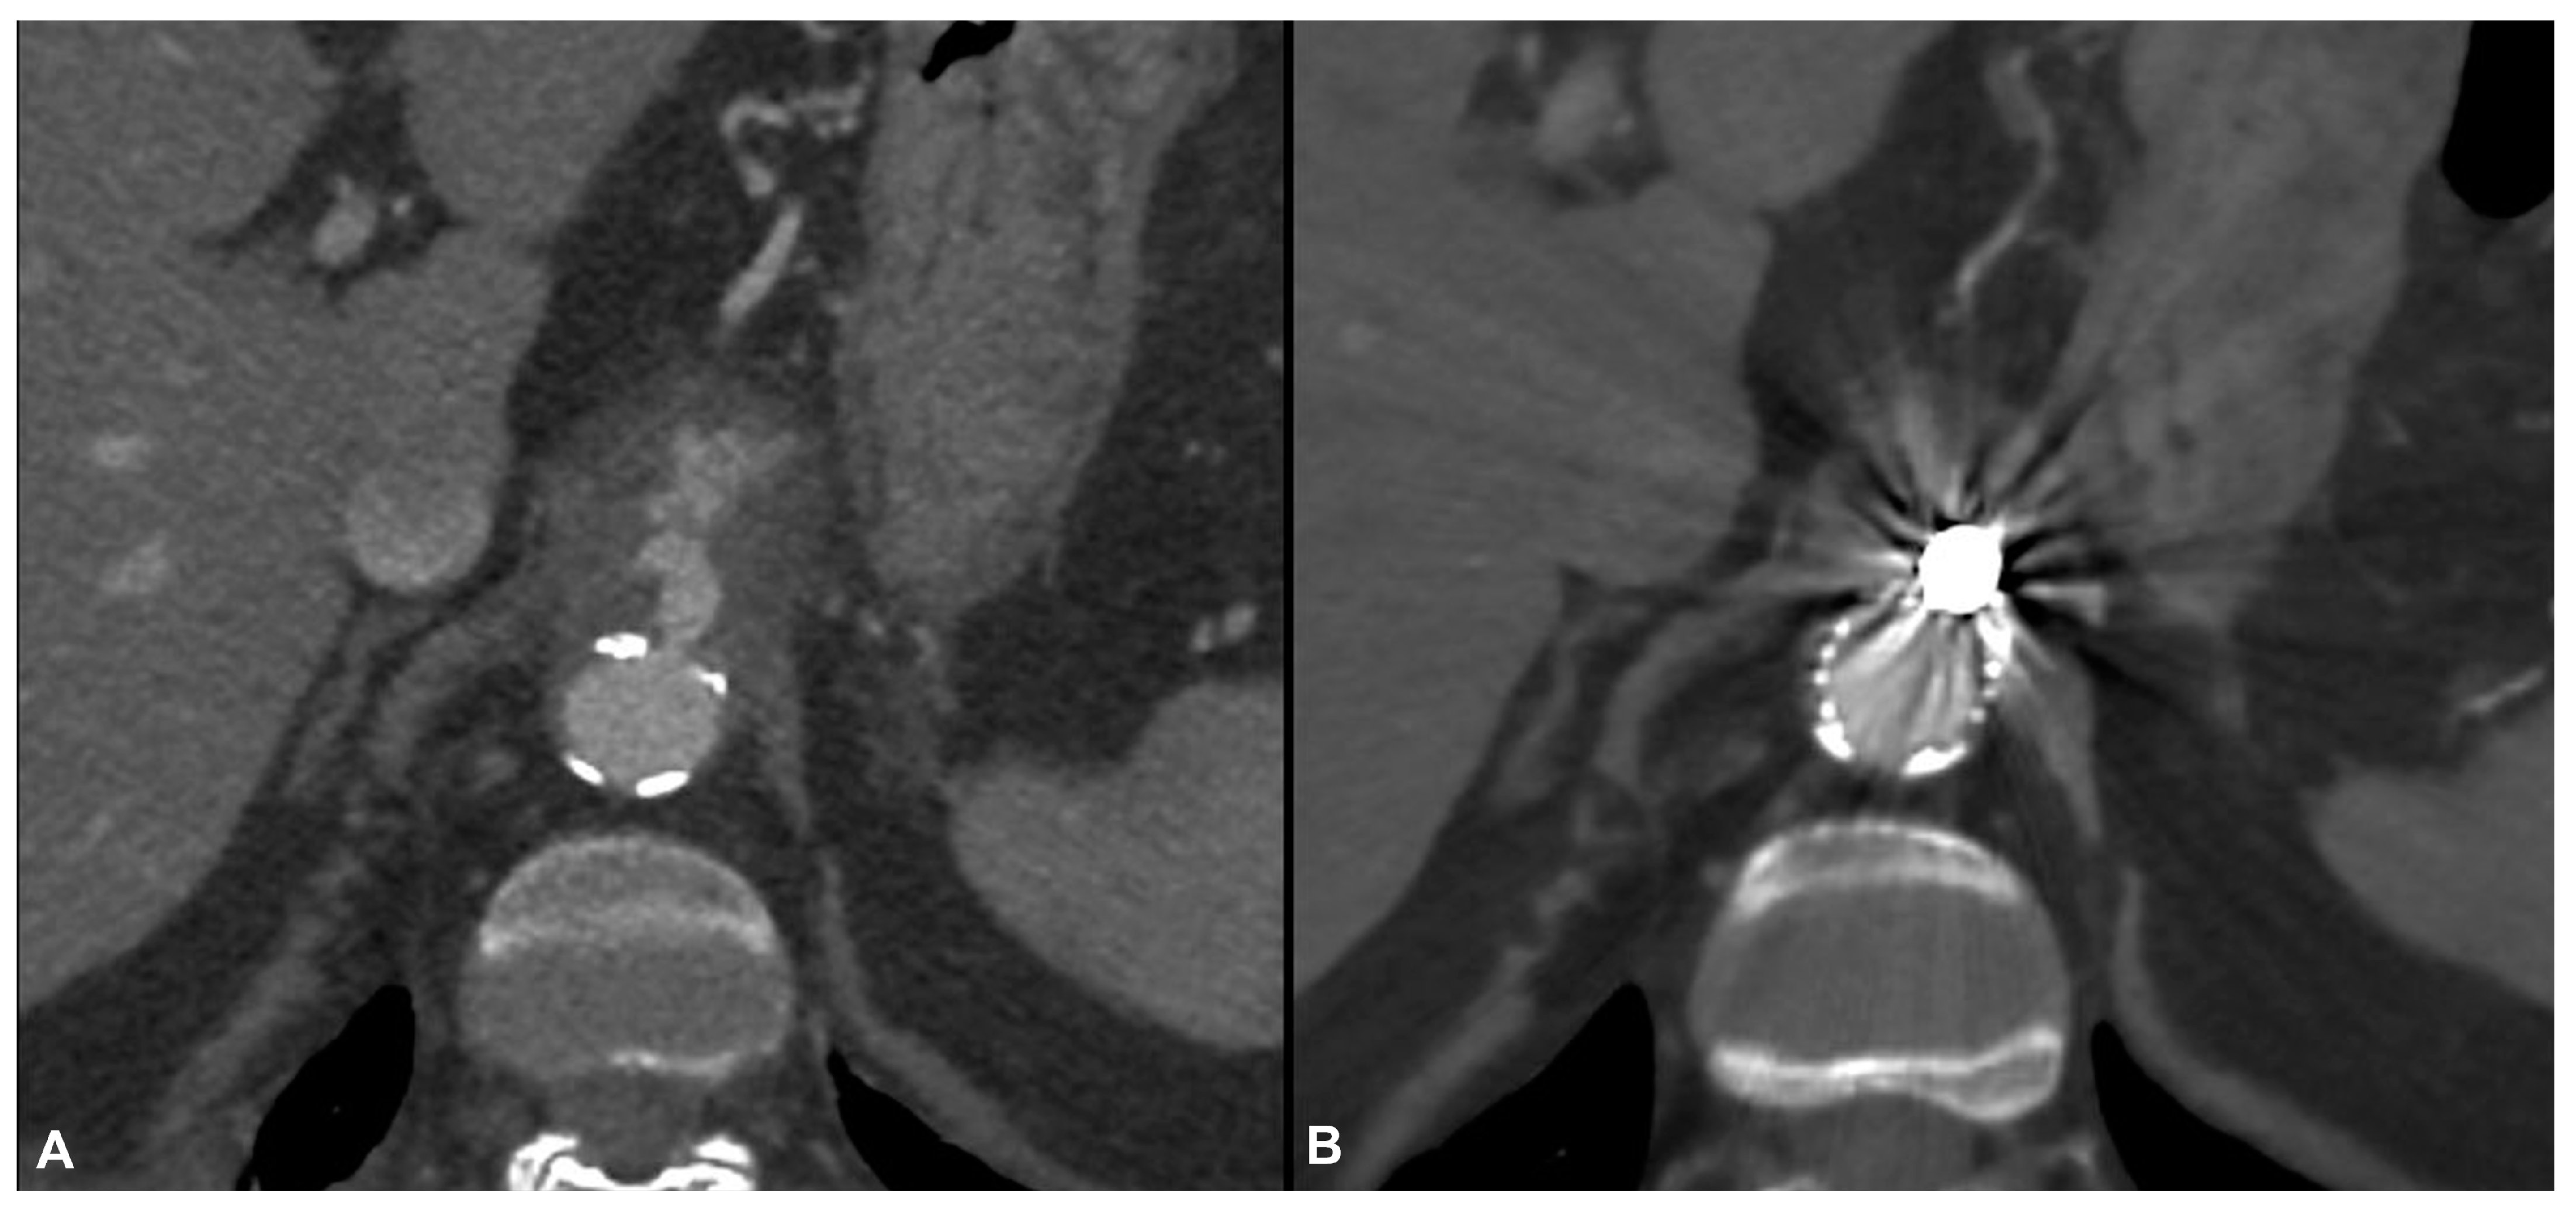

| 13 | M | 75 | Pancreatitis | Brucella spp. | No | Ruptured juxtarenal pseudoaneurysm | Doxycycline | Ch-EVAR | Alive | 60 | Stability | - |